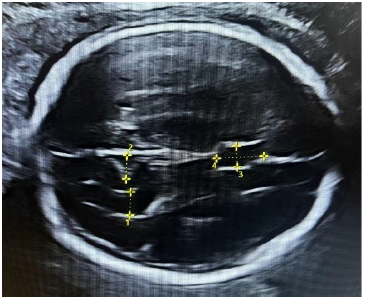

Measurement protocol: A standard transthalamic plane of the fetal head was used as the initial imaging plane for measuring BPD and HC. In this plane, the depths of the insula and Sylvian fissure were recorded (Figure 1). Subsequently, the probe was cranially adjusted to acquire a transventricular plane, where the depths of the POF, lateral ventricle, and the CSP width were measured (Figure 2).

Figure 1. Transthalamic plane showing measurement of (1) HC, (2) BPD, (3) SF, and (4) insula